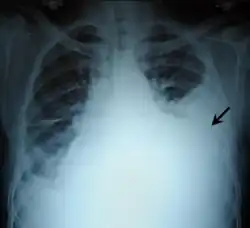

Pleural effusion

.jpg)

A pleural effusion is an accumulation of fluid inside the pleural space. If this collection of fluid gets large enough, it can also push structures in the chest away from it and cause a mediastinal shift. However, a pleural effusion can also pull the mediastinal structure towards itself. If this is the case, then there is an underlying condition causing the collapse of the lung on that side. An example is a tumor obstructing a bronchus and causing lung collapse and pleural effusion.[3]